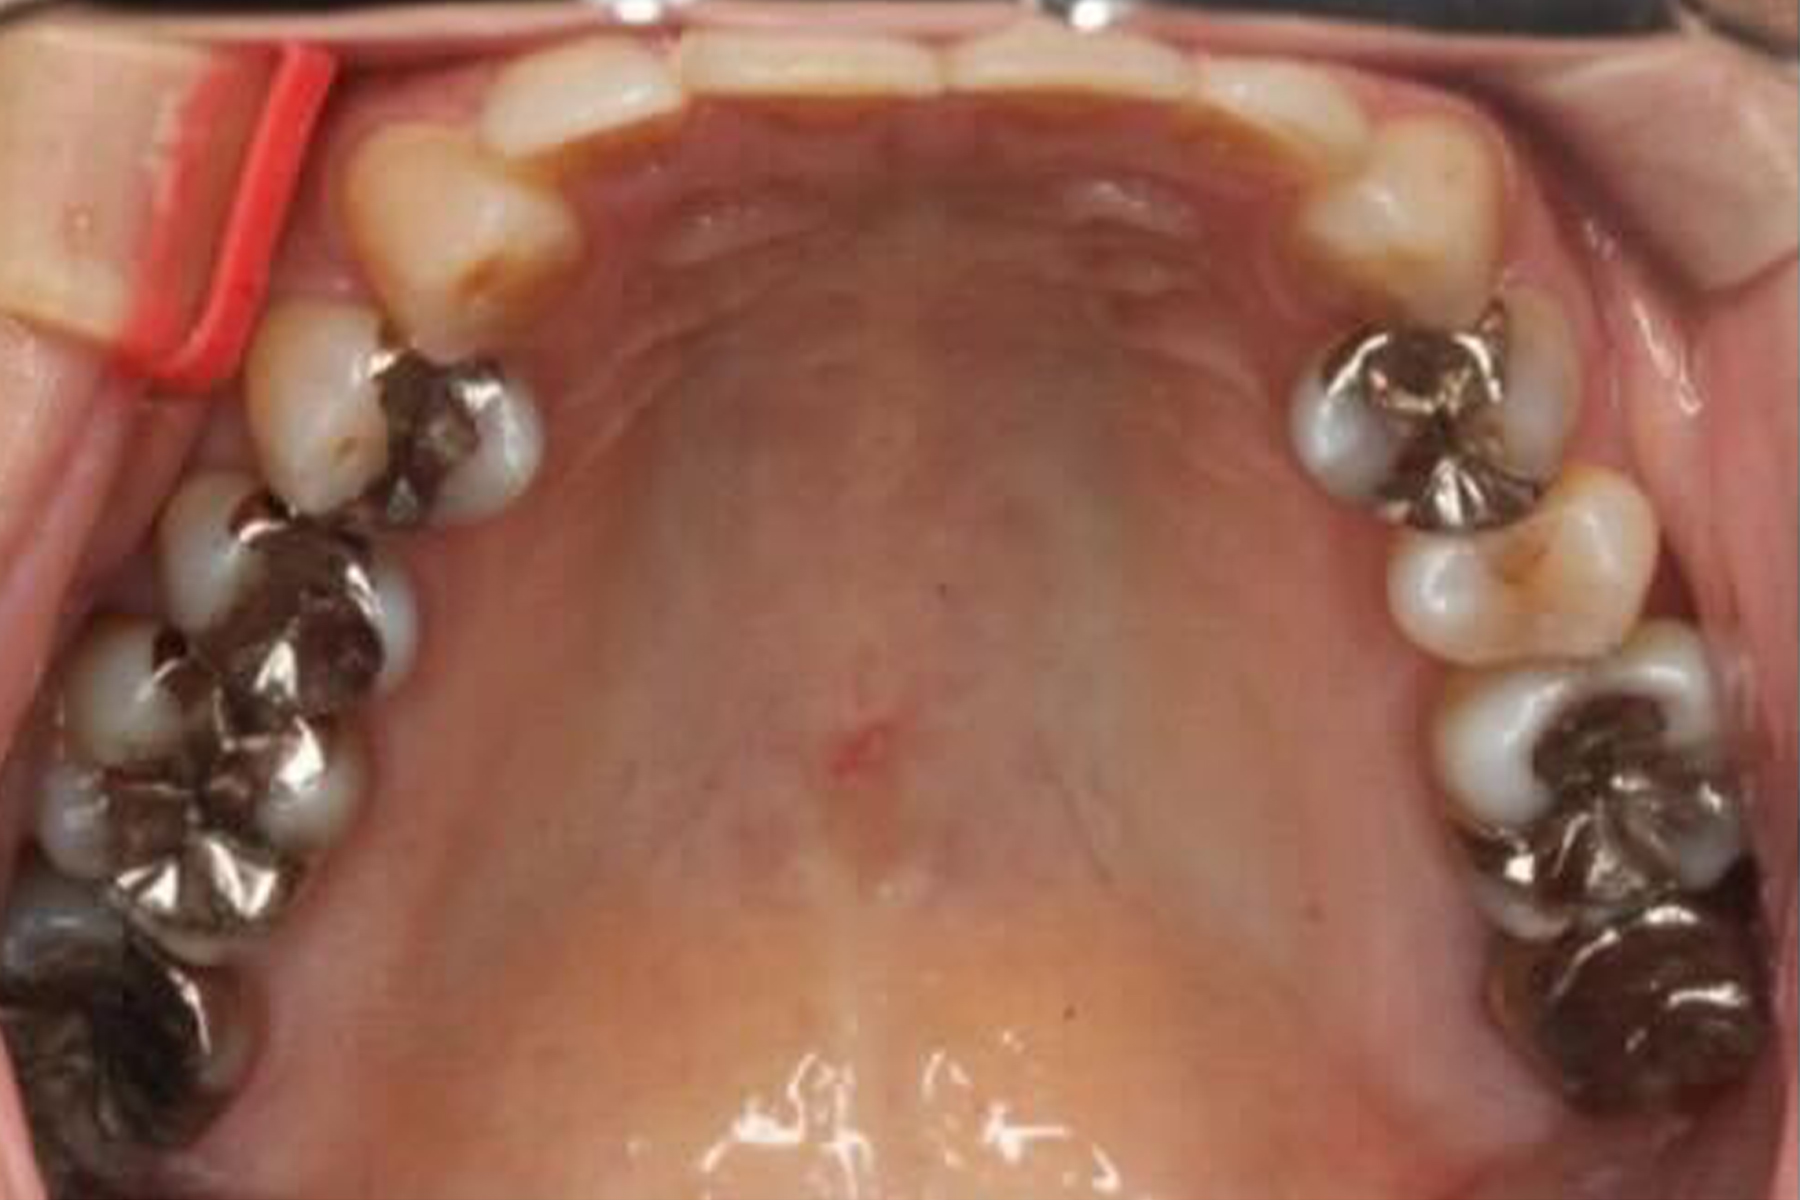

BEFORE

| 主訴 | 銀歯を白い歯に変えたい |